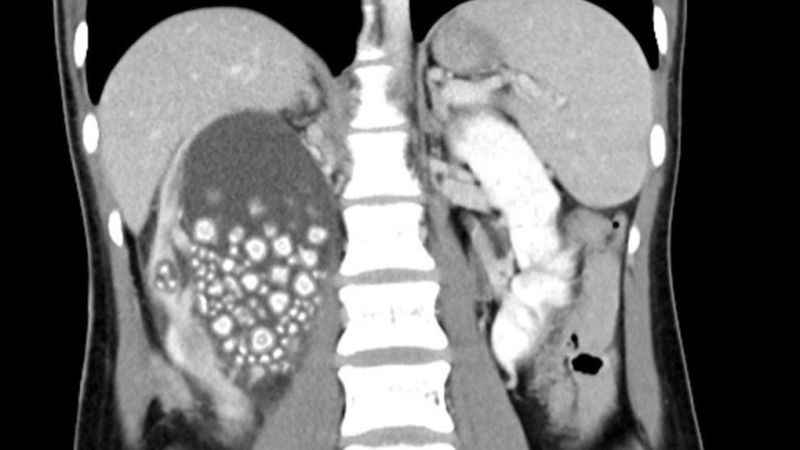

Böbreklerinden 300 adet taş çıkarıldı!Tayvan’nın Tainan şehrinde sırt ağrısı şikayetiyle hastaneye başvuran 20 yaşındaki Xiao Yu’nun böbreklerinden 300’den fazla böbrek taşı çıkarıldı.

Tayvan’ın güneyinde yer alan Tainan şehrinde 20 yaşındaki Xiao Yu sırt ağrısı şikayetiyle hastaneye başvurdu. Yapılan tetkiklerin sonucunda böbreklerinde çok sayıda böbrek taşı tespit edilen Yu acil ameliyata alındı. Başarılı geçen ameliyatın ardından Yu’nun böbreklerinden 0.5-2 cm boyutlarında 300’den fazla böbrek taşı çıkarıldı.